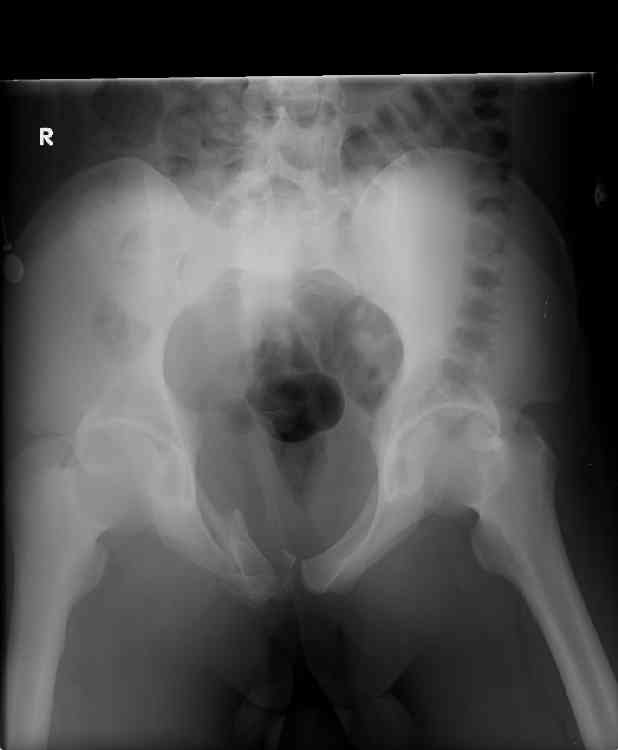

this is a healthy 22yo male. peds vs auto.

no other injuries. has anyone treated these non-operatively? thanks.